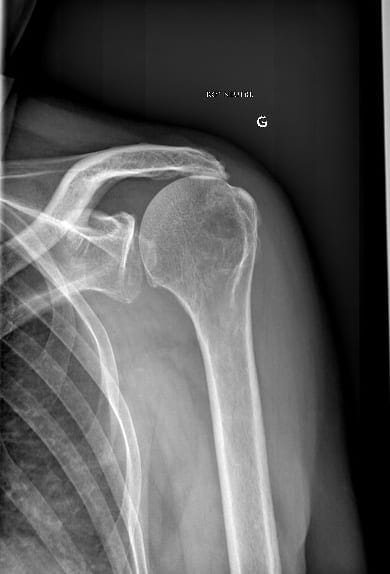

Omarthrose centrée de l’épaule

Les radiographies standards sont souvent suffisantes pour poser le diagnostic d’omarthrose. Elles permettent également de préciser s’il s’agit d’une omarthrose centrée c’est-à-dire primitive ou d’une omarthrose excentrée liée à une rupture ancienne de la coiffe des rotateurs qui entraîne une ascension de la tête humérale vers l’acromion. Elles permettent également de localiser la présence d’ostéophytes qui sont des excroissances osseuses générées par l’arthrose, de visualiser du matériel chirurgical (clou, plaque, vis) liés à une intervention précédente pour une fracture par exemple.